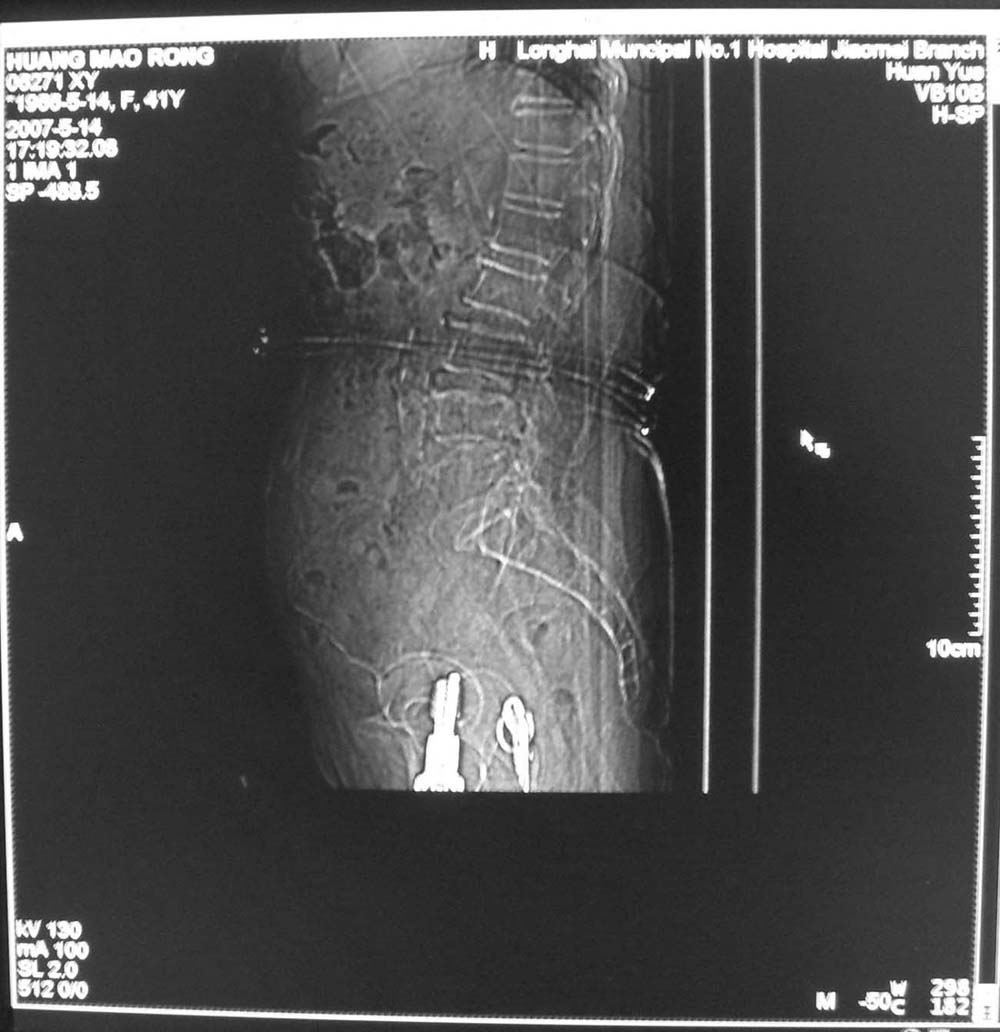

以下是引用jiangjing在2007-5-16 11:05:00的发言:[br]zhichi [br]ct所见:[br]l4-5椎间盘膨出,双侧黄韧带增厚,致使对应椎管变窄,硬膜囊受压.[br][br]l5-s1椎间盘后突,其后硬膜囊受压.l3-4椎间盘未见突出征象.[br]诸椎体边缘及对应椎小关节突骨质增生.腰椎生理曲度正常.[br]腹主动脉壁广泛钙化.[br]印象:[br]1、l4-5椎间盘膨出并双侧黄韧带肥厚及椎管狭窄。[br]2、l5-s1椎间盘突出。[br]3、腰椎及椎小关节退变。